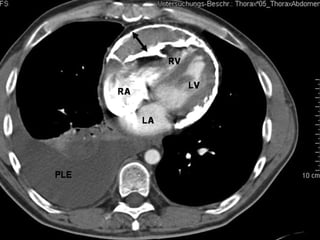

CT scan performed during an infusion of contrast material shows enhancement of the soft-tissue-

density pericardium (arrowheads), which is up to 6 mm thick.

   Panel A. Echocardiographic transmitral flow

pattern with exaggerated respiratory variation in

inflow velocities (>25%).

   Panel B. Transaxial CT image (slice thickness

3.0 mm) of the heart at mid-ventricular level,

demonstrating severe calcification of the

pericardium (arrows). In addition, bilateral pleural

effusion is seen. AO, descending aorta; PE,

pleural effusion.